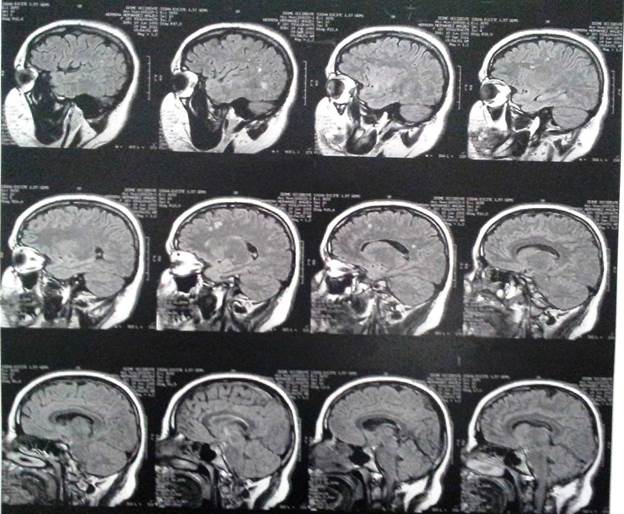

Three years after the first consultation, bilateral T2 hyper-intense focal lesions and bilateral FLAIR frontal/parietal subcortical lesions, nonspecific in character, most likely as sequelae, were observed (Fig. 1).

Imaging findings

MRI findings include hyperintense areas of diffuse, bilateral, and often symmetrical demyelination in the periventricular white matter and cerebellum that may converge with dis ease progression, with frontal predominance in the late stages (juvenile forms and in adults).2,7,12

On CT, hyperdensities are observed in white matter, par ticularly in the frontal and parietal regions. As it progresses, cortical and subcortical atrophy is observed, with ventricu lar dilatation. Areas of hypodensity reflect loss of myelination and cerebroside accumulation.1 A "tigroid" or "leopard skin" appearance has been described, with hypointense bands (normal white matter) within T2 hyperintense areas of abnormal white matter (areas of demyelination).2

There is evidence of significant loss of grey matter volume from early stages of MLD. In adults, there is a more pronounced general cortical atrophy of both grey and white matter and a more pronounced cortical reduction in cingulate gyrus and frontal lobes.3

MRI is more sensitive than CT in the detection of lesions in the white matter and it is useful for visualising early-onset lesions in regions of the posterior fossa (brain stem or cerebellum); it also shows the severity and extent of the disease.4

Although cases of MLD have been reported in relatives,18 most cases, such as the one presented here, correspond to only one affected person in the genogram. The initially negative findings in diagnostic imaging and the subse quent presence of lesions on the MRI showed the clinical progression.